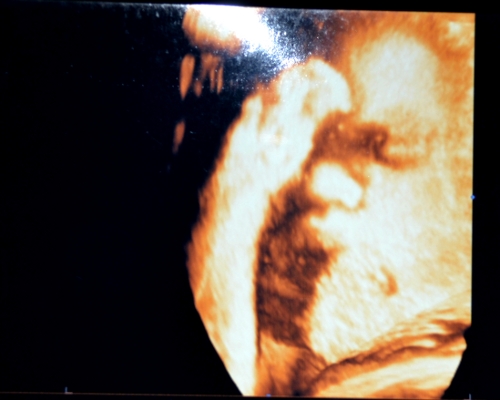

3Д, здесь прикол, масик отдает нам честь

рука ко лбу прислонена, закрывает личико немного, но мне все понятно на фото, и видно, глазки, носик и раздутую губу, а губа такая, потому что когда делали фрагменты, он постоянно открывал рот и шевелил губами, толи зевуху делал, толи глотал амн.жидкость, но так это трогательно было, чуть не прослезилась, сладкий мой мальчик